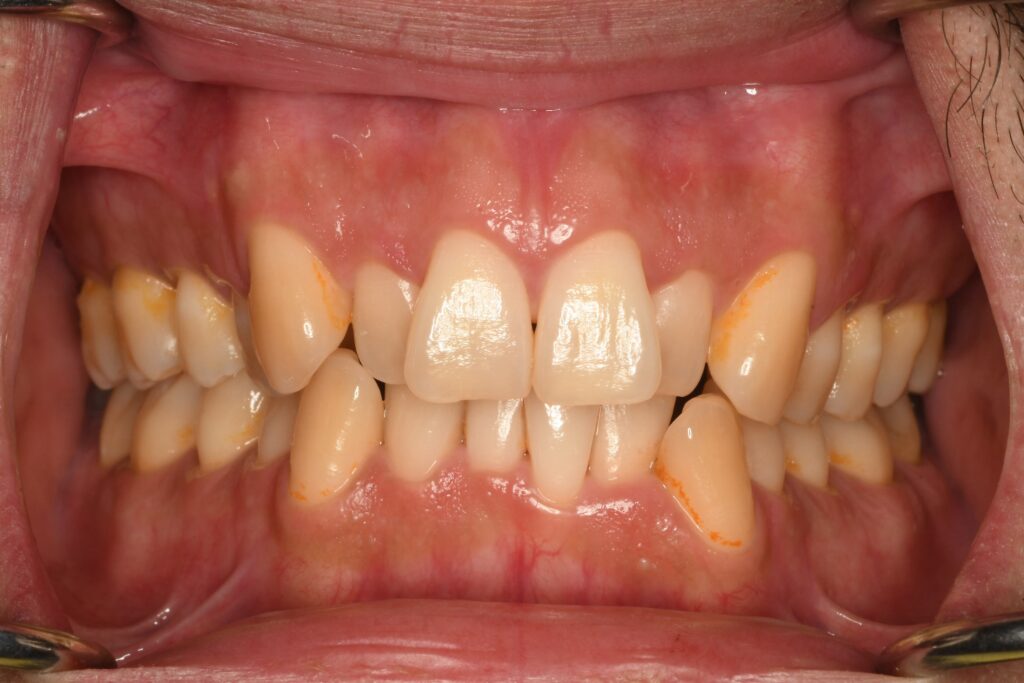

前歯が凸凹しているのが気になる40代男性のケースです。このようなケースに関わらず、矯正治療は隙間をどうするのかがメインテーマです。今回の場合は、顎の大きさと歯の大きさのアンバランスと奥歯が前の方に位置して生えてきたことが原因と思われます。あくまでも予想です。この予想がそうだねってなるためには精密検査が必要です。

検査をした結果、奥歯が前に生えてきたことで前歯の空き場が少なくなって凸凹になったようです。今回の治療計画は、親知らずが上下左右に生えているので4本の親知らずを抜いて、その隙間を利用して歯並びを整えることにしました。